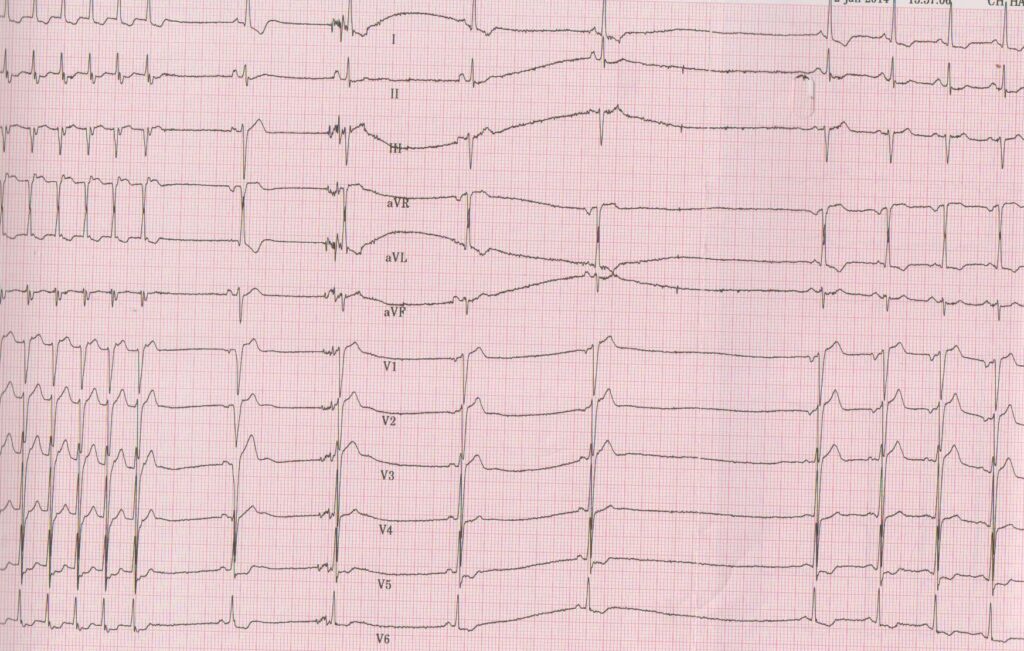

Ce type de tachycardie présente certaines caractéristiques électrocardiographiques: • L’électrocardiogramme entre les crises est le plus souvent normal;

• La fréquence de la tachycardie peut varier d’un patient à l’autre (entre 130 à 250 bpm); elle est généralement très rapide chez l’enfant (> 200 bpm) et plus lente chez les personnes âgées (< 150 bpm) quand la conduction nodale est altérée;

• Les QRS sont fins dans la majorité des cas, même si une aberration de conduction est possible; une alternance des QRS peut être observée sans être spécifique;

• Conduction auriculo-ventriculaire 1/1; les ondes P’ sont rétrogrades et peuvent se superposer à la partie terminale du QRS; elles sont alors difficilement identifiables; la primo-dépolarisation atriale est antéro-supérieure (à l’émergence de la voie rapide); elles peuvent modifier la morphologie du QRS (en comparaison avec les complexes d’origine sinusale) avec un aspect caractéristique de pseudo-onde S dans les dérivations inférieures et de pseudo-onde r’ (discret retard droit) en V1 ou en aVR; plus rarement, l’activité atriale peut être positionnée juste avant le QRS; certains aspects électrocardiographiques sont moins typiques avec un bloc de conduction antérograde et 2 activités atriales pour un ventricule;

Description tracé